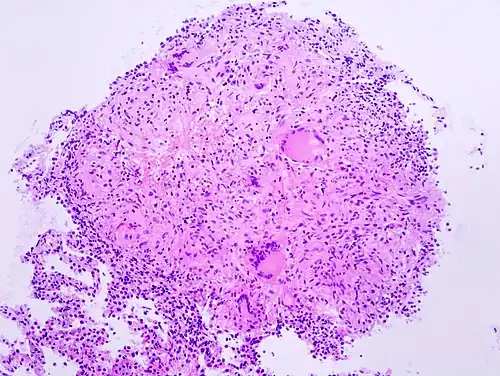

Granulom neboli granulomatózní zánět je zvláštní typ chronického zánětu, při kterém převažují v zánětlivém výpotku aktivované makrofágy epiteloidního vzhledu a lymfocyty a ojedinělé plasmatické buňky. Epiteloidní makrofágy se mohou často spojovat a vytvářet tak mnohojaderné buňky různé velikosti. Typickým příkladem granulomatózního zánětu jsou infekce vyvolané mykobaktériemi – tuberkulóza.